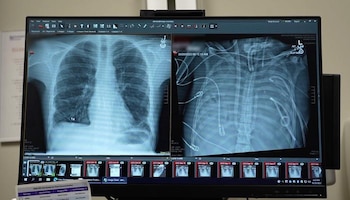

La solución fue radical. El equipo de Northwestern Medicine optó por extirpar ambos pulmones y conectar al paciente a un sistema de pulmón artificial total, un dispositivo diseñado en el propio hospital.

Esta tecnología, denominada “sistema total de pulmón artificial extracorpóreo adaptado al flujo”, no solo oxigena la sangre y elimina dióxido de carbono, sino que también mantiene la circulación sanguínea estable y protege la función del corazón.

A diferencia de técnicas previas como la oxigenación por membrana extracorpórea (ECMO), el nuevo sistema logra que el corazón continúe bombeando sangre de manera eficiente sin los pulmones presentes.

Durante 48 horas, el paciente permaneció sin pulmones, con el tórax vacío y conectado únicamente al sistema artificial. El equipo médico vigiló de cerca su evolución y, al confirmarse la mejoría, logró ingresar al paciente en la lista de trasplantes. Dos días después, se realizó el trasplante doble de pulmón. Más de dos años después del procedimiento, el paciente mantiene una vida normal y sus pulmones funcionan correctamente.

El análisis de los pulmones extraídos reveló que el daño era irreversible. Los investigadores encontraron cicatrices y destrucción del tejido a nivel molecular, lo que, según el especialista, constituye una “prueba biológica de que algunos casos de SDRA no tienen posibilidad de recuperación sin trasplante”.